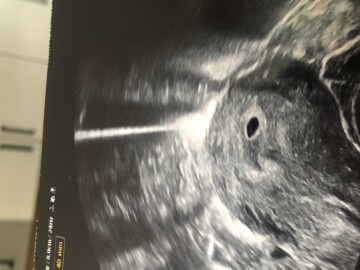

Dobrý den, chtěla bych se zeptat, jestli je mozne videt zloutkovy vacek viz. foto (jde o malou bilou tecku nebo flicek)Jsem nejak 4-5tt

Dobrý den, takto popisovat ultrazvuk z fotografie, navíc v bídné kvalitě, nemůže být směrodatné a přesné, s jistotou je vidět správně uložený gestační váček, s event. možným stínem žloutkového. Obraz bych řekla zcela odpovídá stádiu gravidity, které uvádíte.